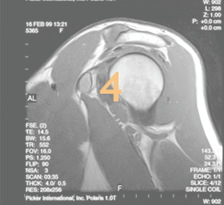

NMR Schulter Bild 5